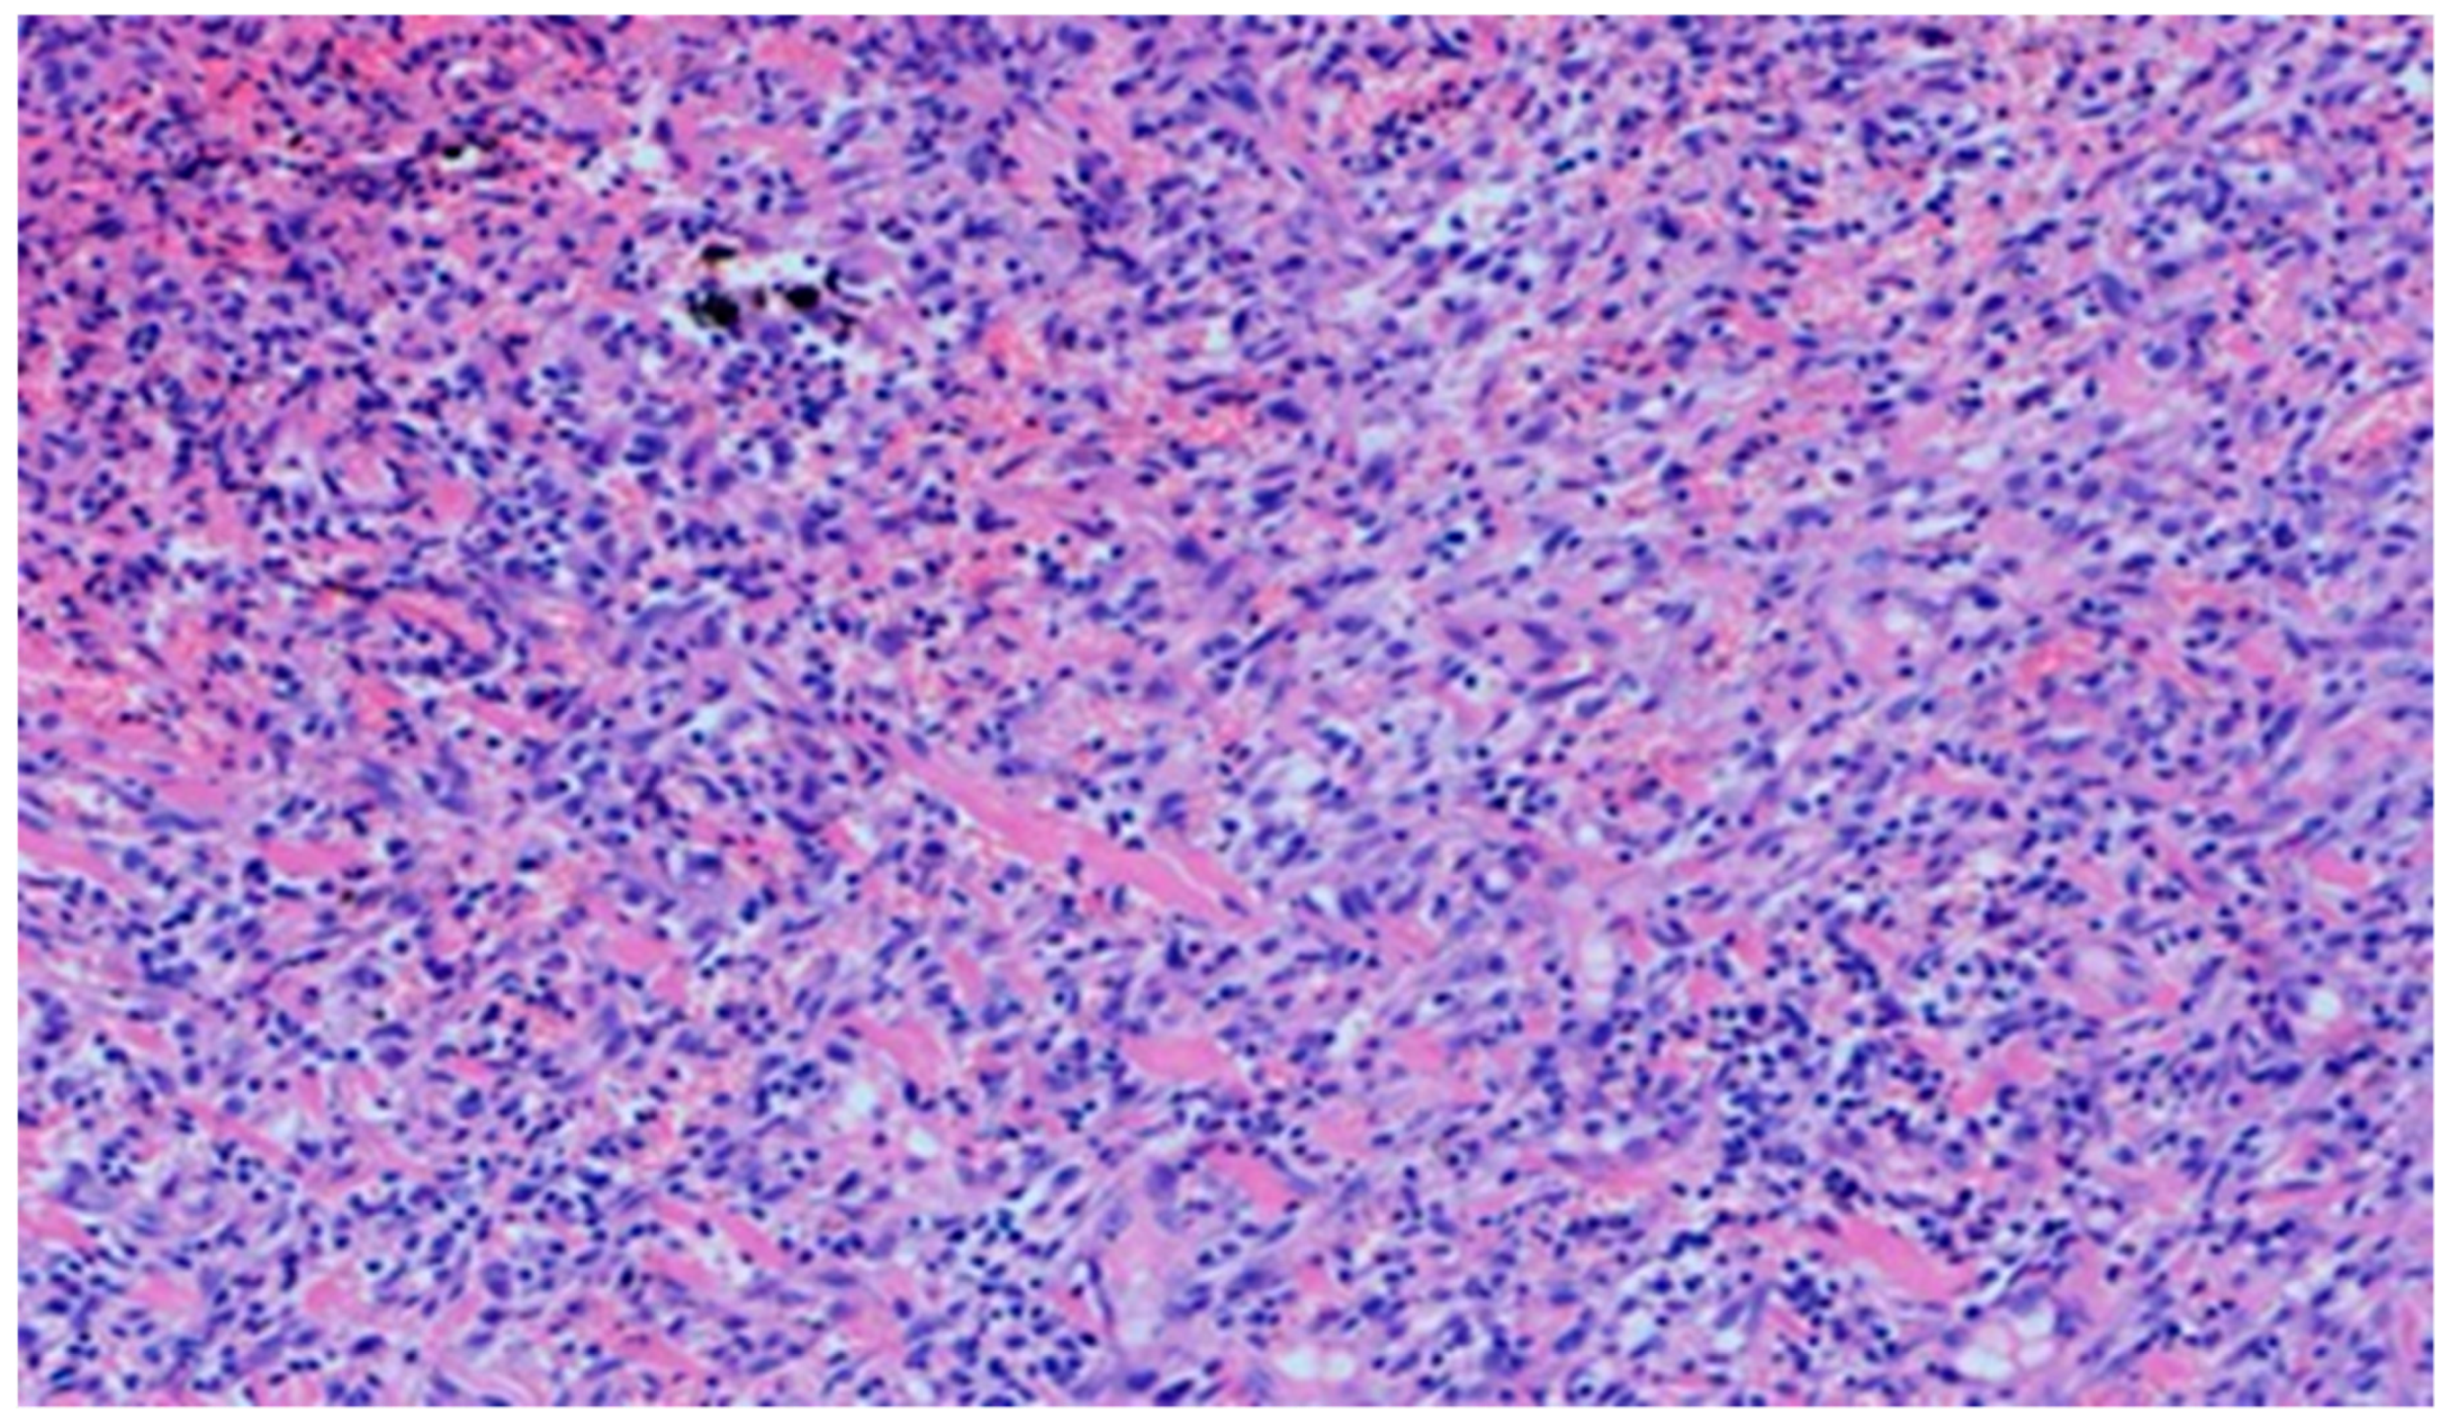

On day 5 of the experiment, slight differences in the wound healing process were observed. Inflammation was present in all wounds and the surrounding tissues, however, with a different intensity, type and depth of infiltration. In group D1, treated with the 1% propolis ointment, there was a moderately dense granulocytic infiltration reaching the dermis. Wounds in group D2, treated with the 1% nanosilver ointment, were characterized by a granulocytic infiltration with a low density and depth of infiltration reaching the dermis. In wounds treated with a mixture of 1% propolis and 1% nanosilver, there was a large granulocytic inflammatory infiltration reaching the depth of the adipose tissue. Wounds treated with sulfathiazole were characterized by a small, mixed infiltration reaching the dermis. On day 5 of the treatment, all wounds from the experimental and control groups did not show any epidermization features. Superficial necrosis was low in the experimental groups and a high degree of necrosis was observed in the sulfathiazole-treated control group. The histopathological findings from day 5 are presented in Table 8 and Figure 13 and Figure 14.

Figure 13. Granulocytic inflammatory infiltration on the border of the dermis and subcutaneous tissue (100×, H-E), in the wound treated with the ointment with 1% propolis and 1% nanosilver, on day 5.